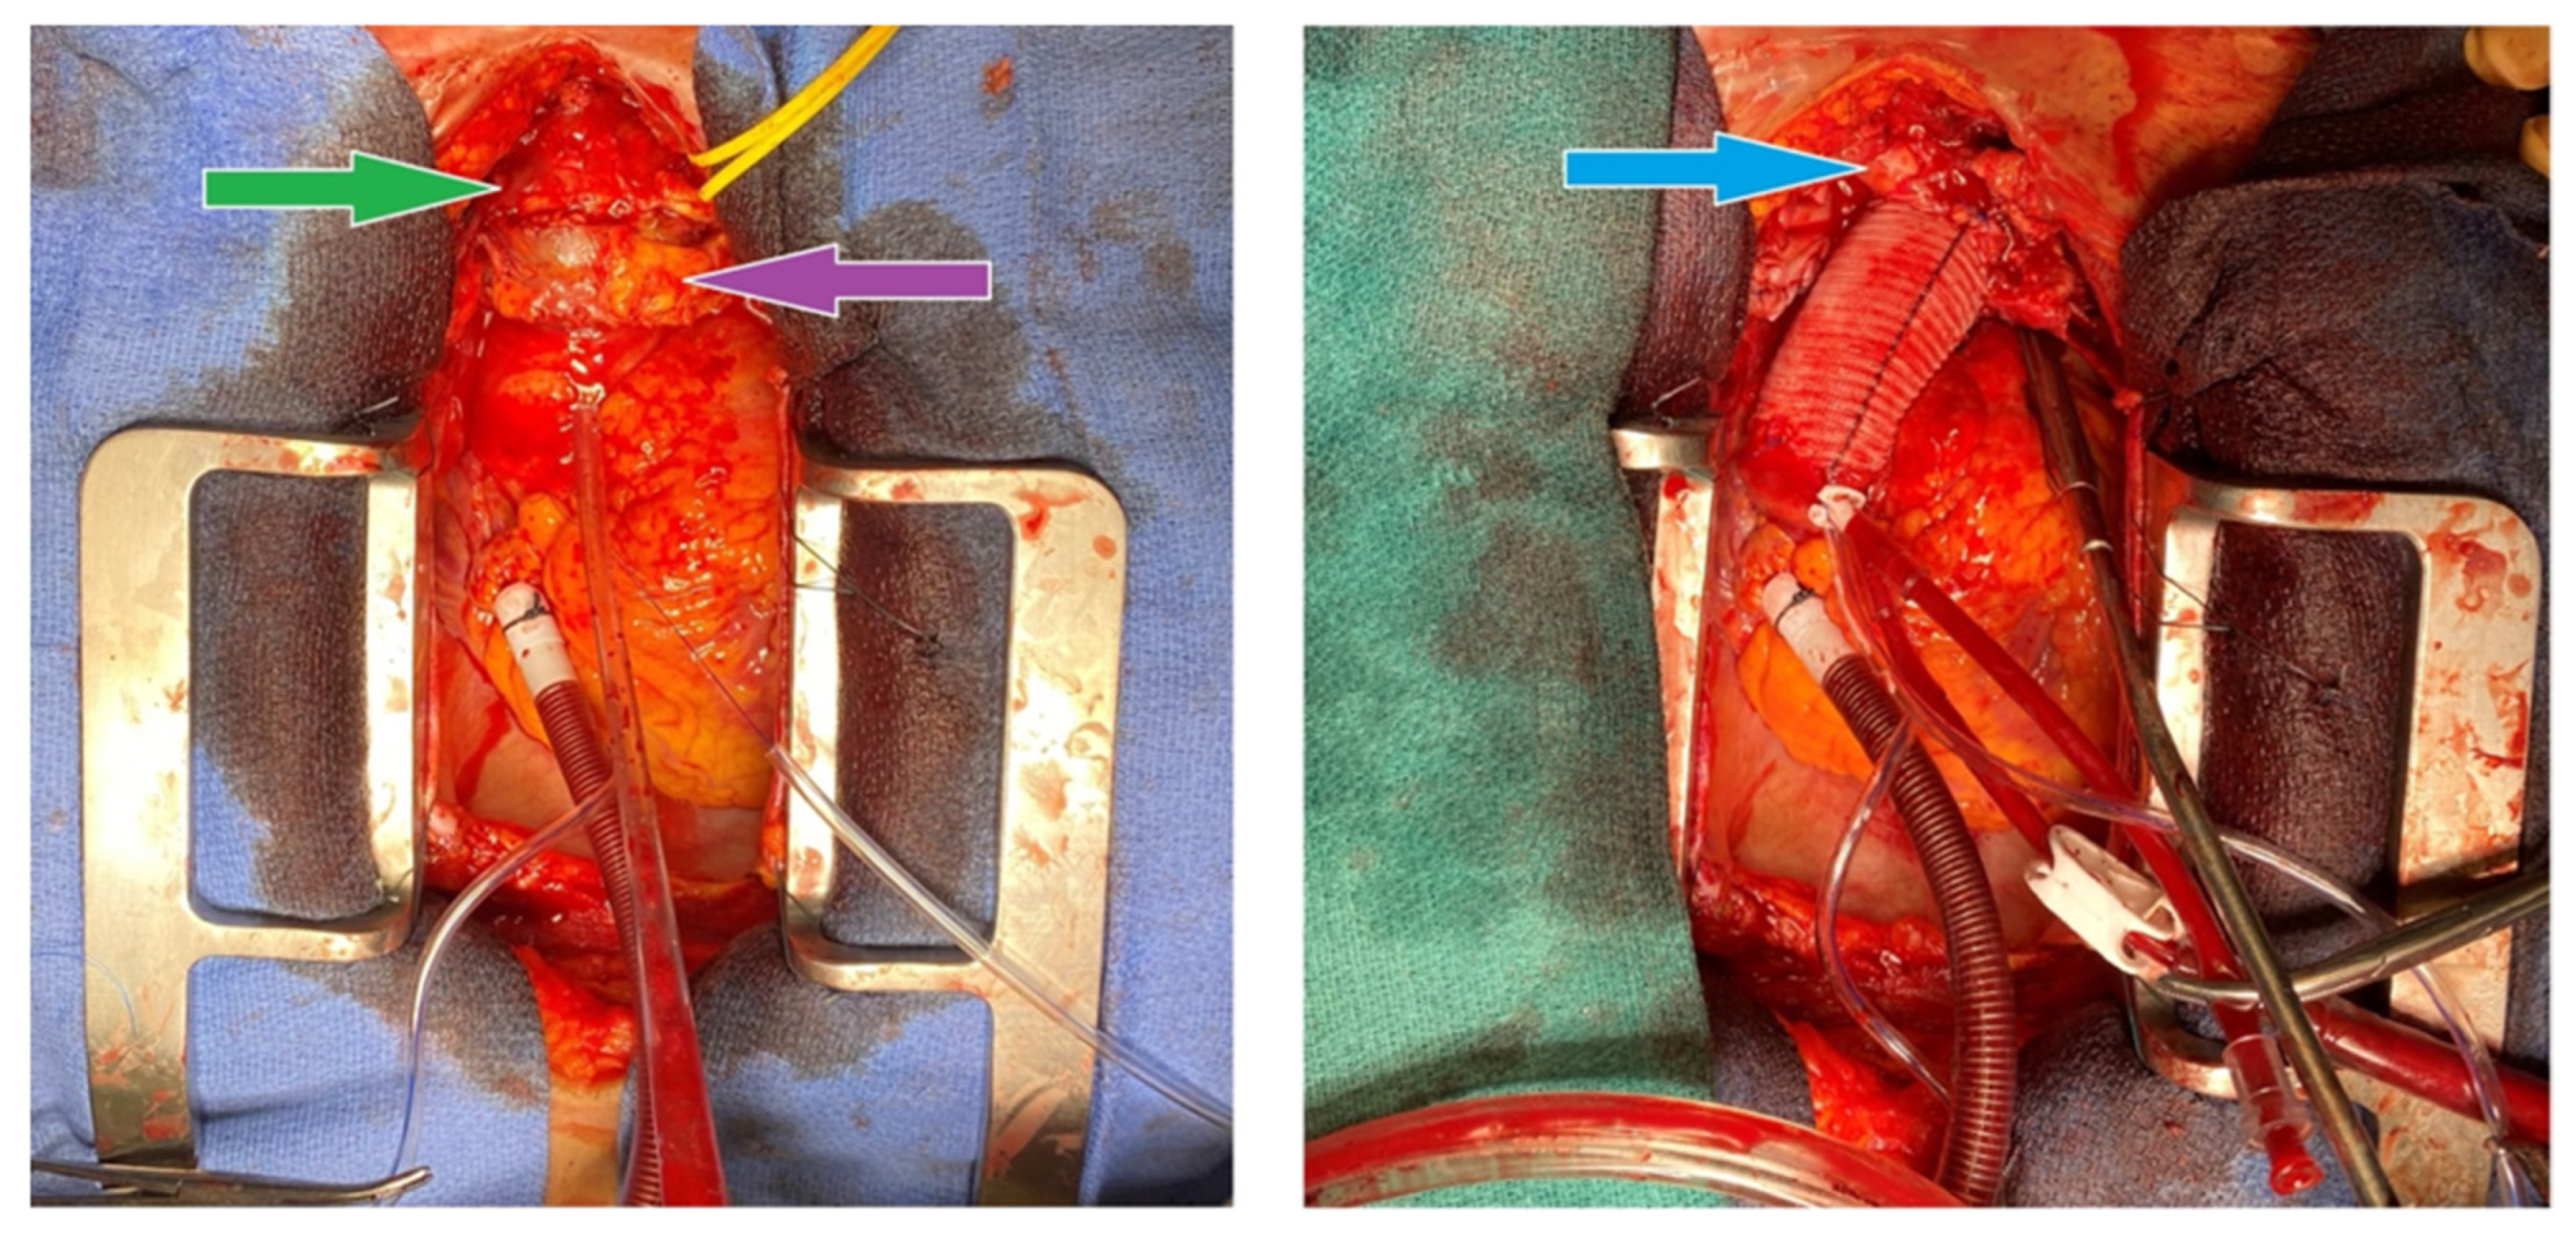

An index procedure debranching the left carotid artery was first performed by vascular surgery, via an end-to-side 8 mm Hemashield graft from the left subclavian to the left common carotid artery. Because catastrophic rupture at sternotomy or during arch clamping could abruptly interrupt antegrade flow to the left hemisphere, this prophylactic carotid–subclavian bypass was created before chest entry to guarantee cerebral perfusion. The extra-anatomic graft, in conjunction with right axillary arterial cannulation discussed in the following paragraph, provided bilateral brain protection while the infected proximal arch was excised and replaced in the second stage of the surgery (Figure 2).

A second operation was performed under cardiopulmonary bypass using a double Y femoral configuration (arterial cannulation at the femoral and axillary sites; venous cannulation at the femoral and atrial sites). Right femoral and right axillary arterial inflows were established through 8 mm Hemashield grafts, while venous return was obtained from the right femoral vein (IVC position) and right atrium. Indeed, we prepared for a high risk of exsanguination intra-operatively. Femoral venous cannulation was instituted before sternotomy to permit the rapid initiation of cardiopulmonary bypass should the aneurysm rupture while opening the chest. After a successful sternotomy and no torrential bleeding, a right-atrial cannula was added to provide bicaval drainage, improve decompression, and maintain optimal perfusion during deep hypothermic circulatory arrest. Total cardiopulmonary bypass time was 200 min, aortic cross-clamp time was 46 min, deep-hypothermic circulatory arrest time was 37 min, selective cerebral perfusion time was 29 min, and the nadir temperature was 19.9 °C.

A pulsatile phlegmon encasing a thrombosed innominate vein was found originating from the base of the innominate artery. Critically, the totally clotted innominate vein was compressing—and thereby tamponading—the mycotic pseudoaneurysm, likely preventing catastrophic rupture before surgery; the vein was completely thrombosed, and when it was dissected, it resulted in an inconsequential rupture of the surrounding thrombus before its removal. No open venous structures were identified as the thrombosed vessel pieces were removed. All clots were removed to further expose the innominate structures, thus uncovering a perforation at the base of the mycotic aneurysm. The distal innominate artery was clamped to permit antegrade brain perfusion via the axillary graft while the patient was in circulatory arrest.

The proximal innominate artery was resected with ectatic tissue from the mid-ascending aorta to the proximal arch. When examined, the phlegmon was found to be perforated. A 30 mm Gelweave (Dacron) graft was sewn end to end to the distal ascending aorta using a running 3-0 Prolene suture; the posterior half of this distal anastomosis deliberately incorporated the rim of the innominate artery defect to create a single, hemostatic suture line (Figure 3). Once the graft was de-aired, it was cross-clamped, systemic perfusion was re-established, and rewarming began. The proximal anastomosis between the trimmed native ascending aorta and the graft was then completed with continuous 4-0 Prolene following a single dose of antegrade cold-blood cardioplegia. Patch repairs were then performed on the right femoral and axillary arteriotomies; the right femoral venotomy was closed with a simple purse-string suture. Intra-operative and post-repair trans-esophageal echocardiography confirmed satisfactory ventricular function and no residual air. Aortic specimens were positive for Streptococcus agalactiae (Group B Streptococcus) on ensuing analysis. Tissue from the distal ascending aorta and proximal arch was sent for histology and culture.

Figure 3. Phlegmon (green) with thrombosed innominate vein (purple) and freed innominate artery post-reconstruction (blue).